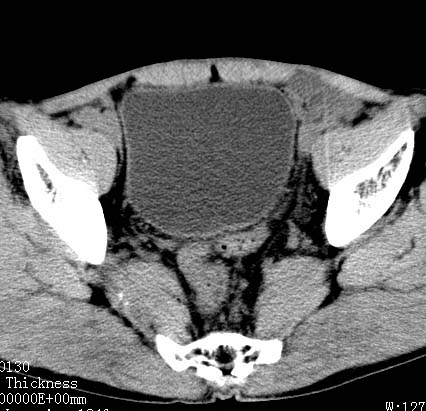

标题: CT17540:男 56岁 . [打印本页]

病人男 56岁 .

前列腺增生,膀胱后壁未见异常,精囊腺及精囊三角未见异常

前列腺增生 钙化!

支持 前列腺增生、钙化。

建议进一步检查除外前列腺癌.

考虑慢性前列腺,精囊炎;不除外前列腺癌

前列腺增生并钙化,可疑直肠占位

前列腺癌.